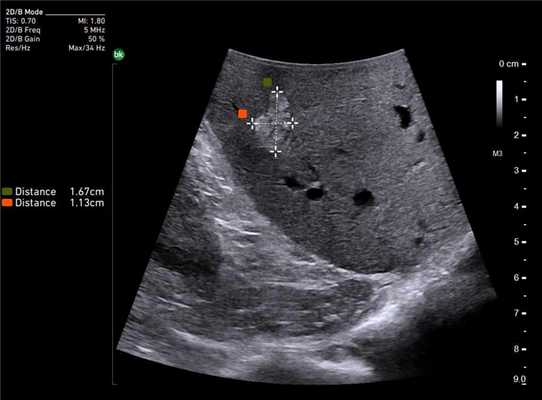

Опухоль почки. Сканирование интраоперационным роботическим датчиком 8826